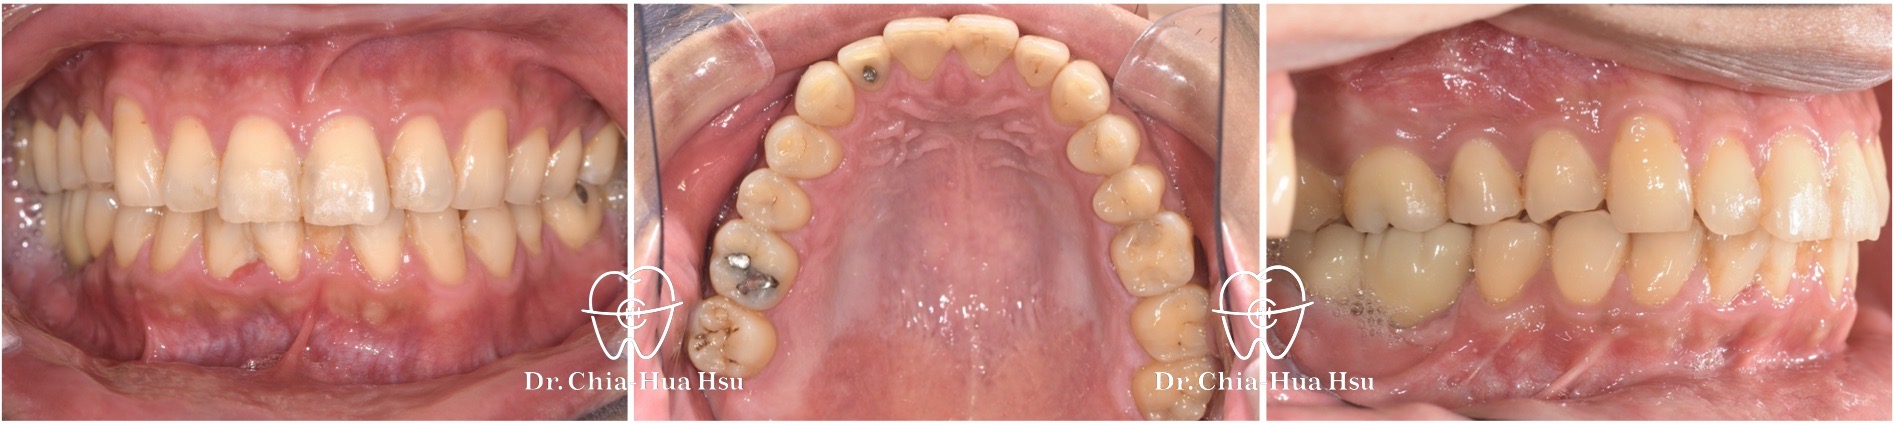

治療前

治療後